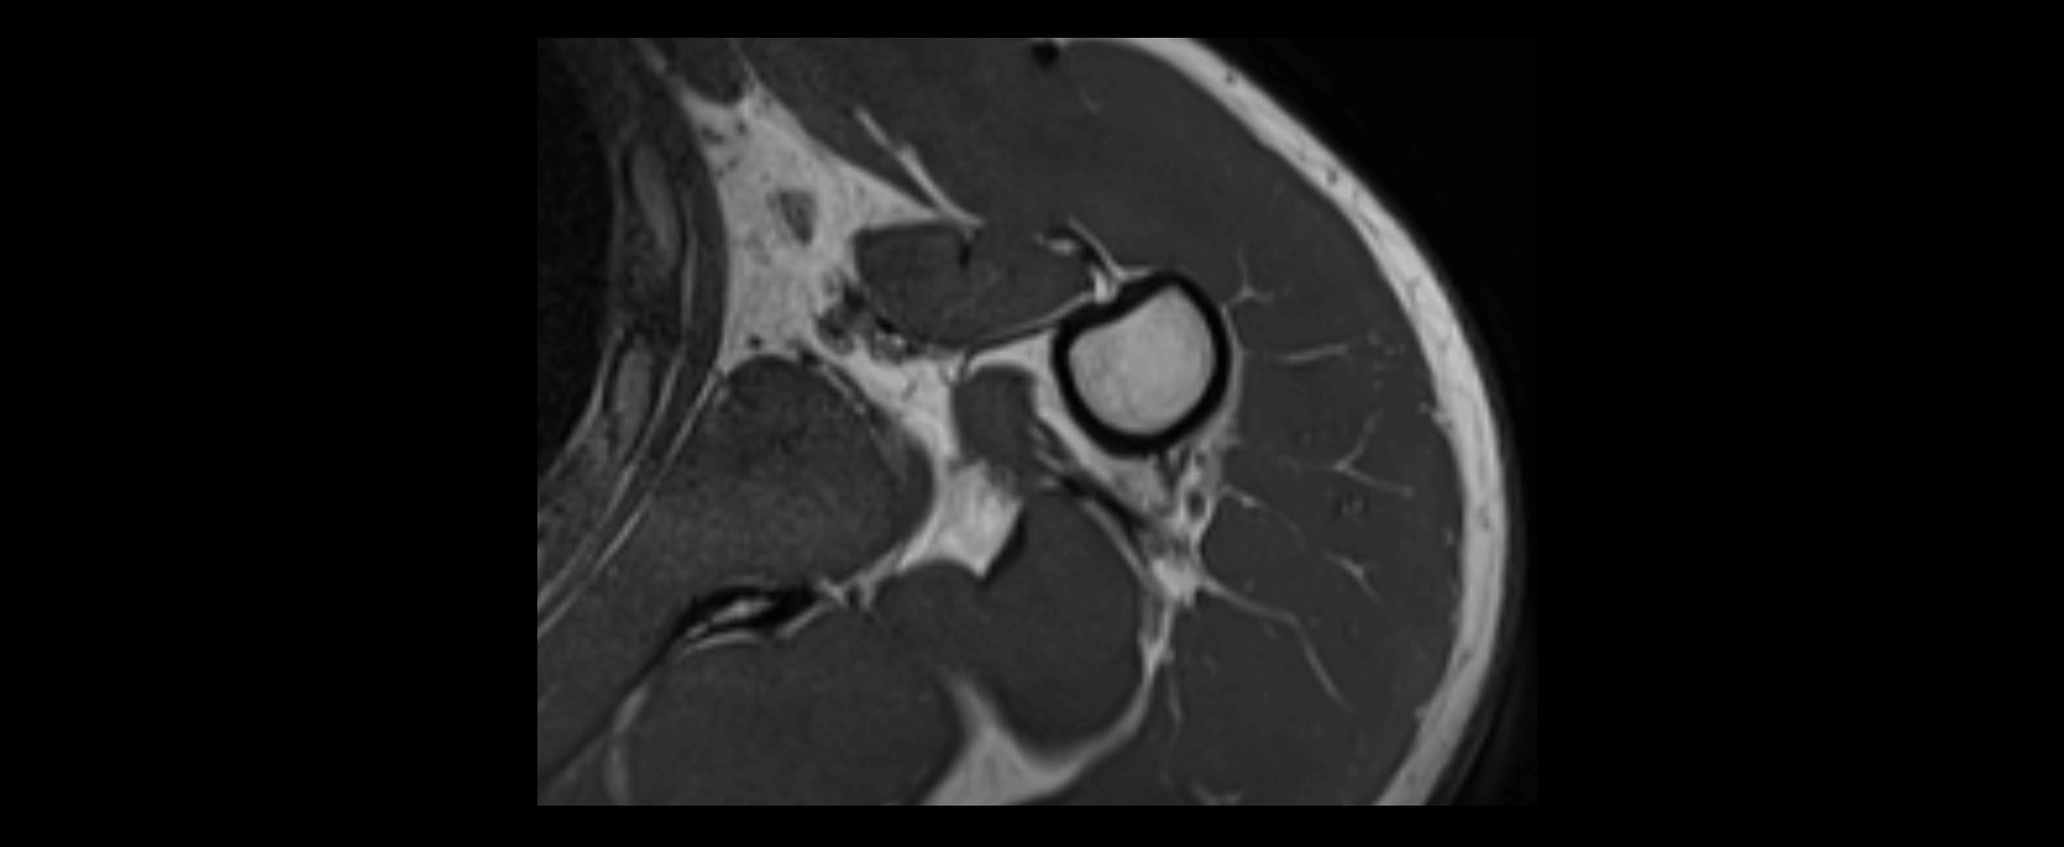

MRI images

image